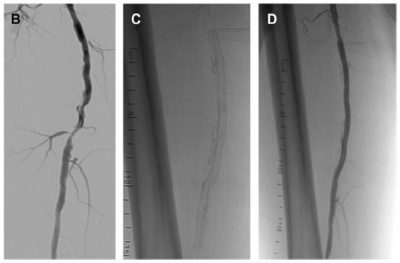

-  أولا: “الدعامه الطرفيه ذات الفتح الذاتي”

– تستخدم هذه الدعامه في الضيق الممتد او الانسدادت الكامله للشريان الفخذي

– من مميزاتها الفتح التلقائي ، انها تأخذ شكل الشريان ، يمكن استخدام البالون لتوسيعها بعد ذلك ، تستخدم في الانسدادات الطويله ، تعالج الانشطار الشرياني بعد توسيع الشريان بالبالون